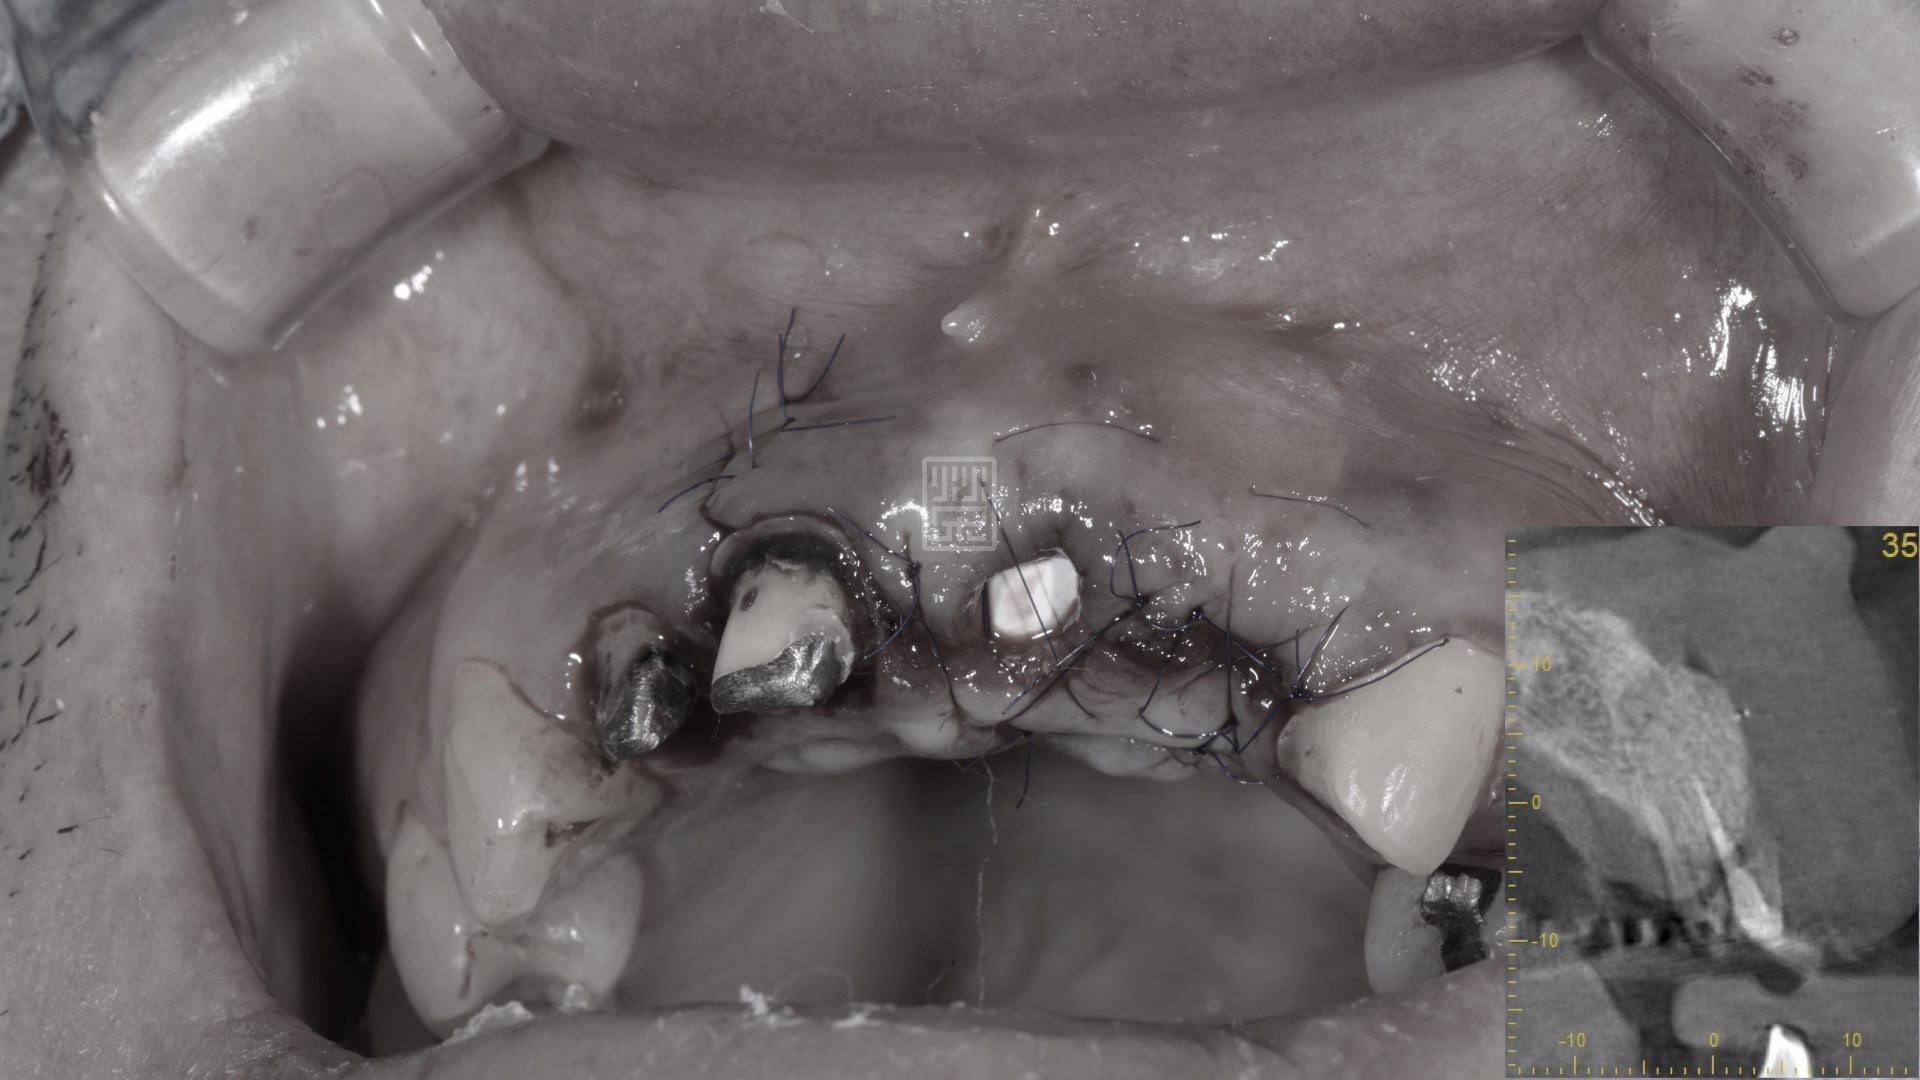

牙根拔除後,發現斷裂處骨頭嚴重缺損

再生醫材補骨

手術後傷口恢復